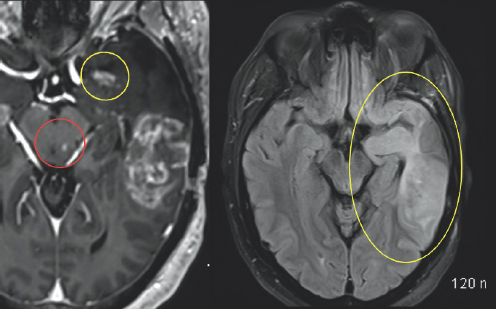

Unfortunately, an MRI scan in October of 2019 revealed worrisome imaging of potential local progression of the tumor (Fig. 2.1–2.3). In addition to this troubling discovery, abnormalities in Columbus’s neuro-cognitive capacity, such as issues with his memory and word-finding capabilities, were gradually becoming more pronounced. This word-finding difficulty showcased itself through his inability to retrieve words for use in regular speech, despite his retention of the ability to understand the English language. To treat these new symptoms, Columbus was put on the steroid dexamethasone.

Variations of gray color are enclosed by a white outline. In the center of the image, there is a very small white blob highlighted by a red circle. In the top right of the image, there is a white colored blob highlighted by a yellow circle. (Right) Gray colored variations are enclosed by a black and white outline. To the right of the image, there is a significantly large white blob highlighted by a yellow oval.

FIGURE 2.2 Brain MRI before surgery. Additional nodular areas of abnormal enhancement that appear bright after being injected with IV contrast are noted in the anterior temporal lobe (yellow circle) and the left aspect of the midbrain (red circle). There is surrounding signal alteration on the MRI sequence image most consistent with swelling (yellow oval).